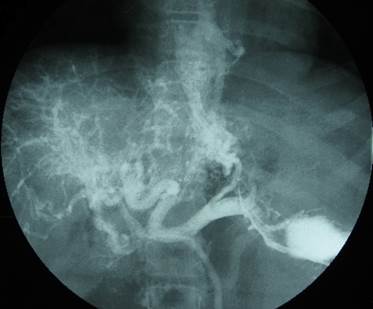

Спленопортография

Рентгеноконтрастное исследование воротной системы позволяет получить наиболее отчетливое представление о состоянии портального кровообращении. Обследование проводится в рентгенкабинете под эндотрахеальным наркозом с деполяризующими миорелаксантами. Пункцию селезенки производится в положении больного на спине, в 10-ом межреберье по средней аксиллярной линии, иглой с мандреном. После прокола передней брюшной стенки мандрен удаляют, иглу вводят в пульпу селезенки на 1,5–2 см. При получении из иглы крови, в нее в зависимости от массы тела ребенка, вводят 30–50 мл подогретого до 37°С контрастного вещества и выполняют серию рентгенограмм. При оценке спленопортограмм обращают внимание на степень расширения селезеночной и ВВ, деформацию сосудистого рисунка печени, забрасывание контрастного вещества в ветви ВВ и состояние коллатеральных путей кровообращения (рис. 1).

Рис. 1. Спленопортограмма. Кавернозная трансформация воротной вены при ПФПГ.

Таким образом, ультразвуковые методы обследования позволяют оценить состояние сосудов печени и селезенки, характер и скорость кровотока в ВВ, наличие и характер коллатералей. Спленопортография показывает точную локализацию блока, анатомическую архитектонику сосудов, диаметр селезеночной и воротной вен, наличие коллатералей и путей окольного кровообращения. Рентгенологическое исследование помогает выявить гастро-эзофагеальный рефлюкс и варикозные вены в пищеводе, оценить состояние его функции. Протокол эндоскопического обследования всесторонне характеризует варикозно расширенные вены пищевода и состояние слизистой оболочки. Указанные методы исследования позволяют определить наиболее рациональную тактику лечения и оптимальный метод хирургического вмешательства для каждого больного.